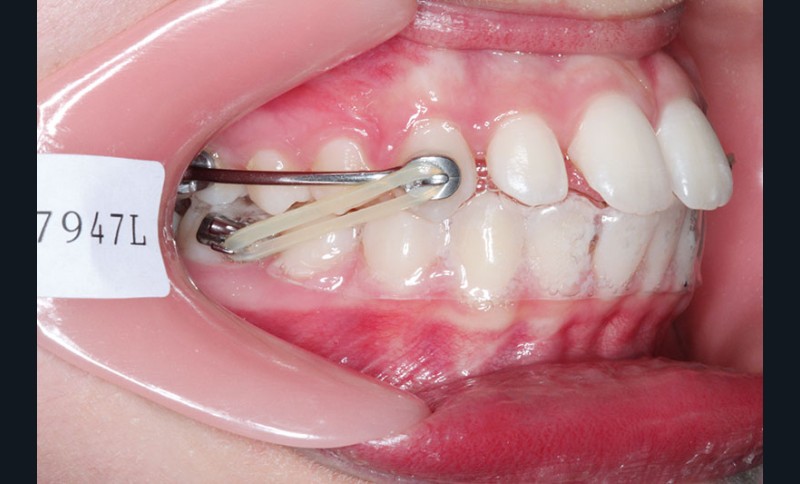

Le pronostic de correction de la classe II est favorable mais il est très important de souligner la vestibuloversion incisive mandibulaire et le risque parodontal associé (fig. 1 à 3).

Il a été décidé de mettre en place un système de correction de la classe II “Motion Classe II Carriere” composé de bras latéraux reliant canine et molaire et d’élastiques de classe II ancrés sur des tubes molaires sur 36 et 46 et une gouttière thermoformée portée en permanence. sAprès dérotation des 16 et 26, recul des secteurs latéraux et libération de la croissance mandibulaire nous mettrons en place un système multiattache autoligaturant passif Carriere SLX 022×028 avec la séquence d’arcs suivante :

1re phase : le Motion Appliance Carriere

Afin d’obtenir la correction de la classe II, nous avons fait porter pendant 3 mois une mécanique d’élastiques intermaxillaires, jour et nuit, avec la séquence suivante (fig. 4):